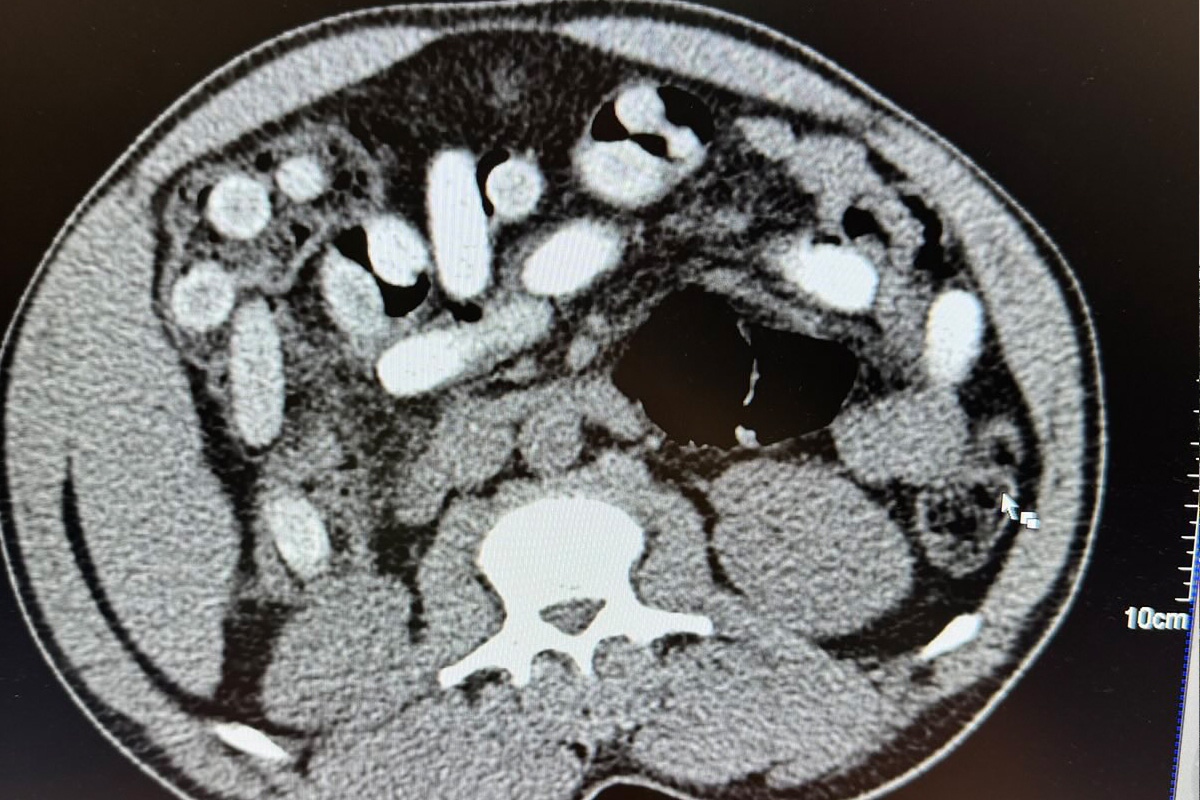

Die radiologische Untersuchung bestätigte den Verdacht. (Bildquelle: Hauptzollamt Köln)

"Die Röntgenaufnahme in einem nahegelegenen Krankenhaus bestätigte letztendlich den Verdacht meiner Kollegen. Der komplette Magen-Darm-Trakt des Mannes war voll mit Drogenpäckchen, sogenannten Bodypacks. In der Größe und Form sind diese mit Datteln vergleichbar."

"Nach dem Ausscheiden der Drogen war klar, der Mann hatte 111 dieser mit Kokain gefüllten Bodypacks geschluckt. Rund 1,3 Kilogramm Kokain versteckt im Körper ist für uns ein neuer trauriger Rekord."